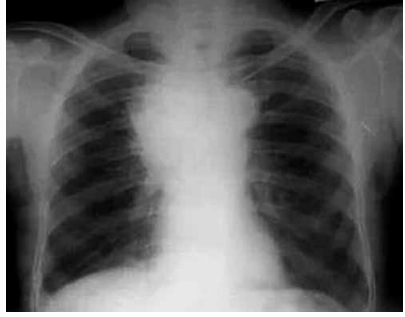

Paciente com 67 anos, tabagista, procura atendimento

em unidade de pronto atendimento. Relata dor precordial e nas costas, há quatro meses, inicialmente de leve

intensidade, mas que está piorando, além de fraqueza

nos membros inferiores e desconforto para engolir. Há

três dias, percebeu inchaço no pescoço, dos dois lados.

Exame físico: hemodinamicamente estável, pletora facial

moderada, edema supraclavicular bilateral, circulação

colateral na metade superior do tórax.

Radiografia de tórax a seguir: